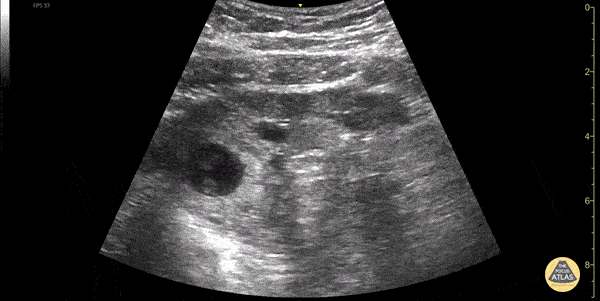

OB/Gyn - Ectopic Pregnancy

30s female currently 7 week pregnant with lower abdominal pain and tenderness to palpation to lower abdomen. POCUS showed a gestation sac containing a yolk sac and fetal pole outside of uterus. Also noted is a thickened endometrial stripe (to the right of the gestational sac). No free fluid was noted in the RUQ. The patient was taken to the OR for definitive management of ectopic pregnancy. Dimitri Livshits DO, Ultrasound Fellow, Kings County/SUNY Downstate; Jane Belyavskaya MD, Ultrasound Fellow, Kings County/SUNY Downstate; Farnam Kazi MD, Ultrasound Faculty, Kings County/SUNY Downstate;